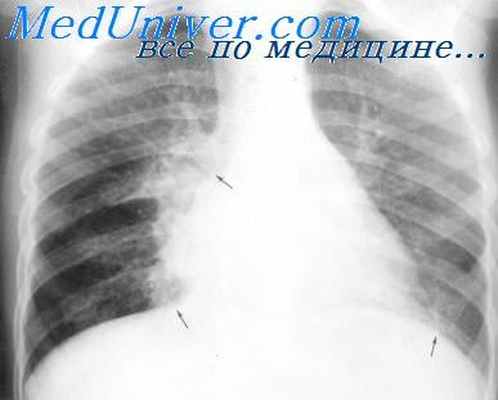

Специальные исследования • Рентгенография органов грудной клетки. «Летучие» инфильтраты при аллергическом бронхолёгочном аспергиллёзе; шаровидное объёмное образование при аспергилломе; узловые или очаговые и сливные инфильтраты, образование полостей при инвазивном аспергиллёзе • Бронхоскопия, бронхиальные смывы, бронхоальвеолярный лаваж или трансторакальная аспирационная биопсия тонкой иглой. Изучение образцов помогает выявить характерные патоморфологические изменения • Открытая биопсия лёгкого позволяет поставить точный диагноз, однако показания к её проведению зависят от состояния больного.